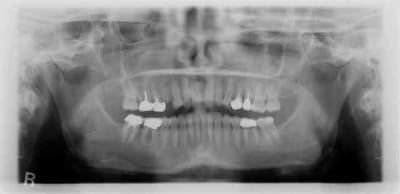

pour la forme et le fond pano avant retro à la pose et rétro aujourd'hui

prévu implant en 36 et l'endo de 15 avait été reprise avant pour être refaite simultanément je connais les critiques nonoliennes.

pour info déja trois cas similaires au maxillaire pas à la mandibule.

et c'est un axiom en 4*12 pas un krestal